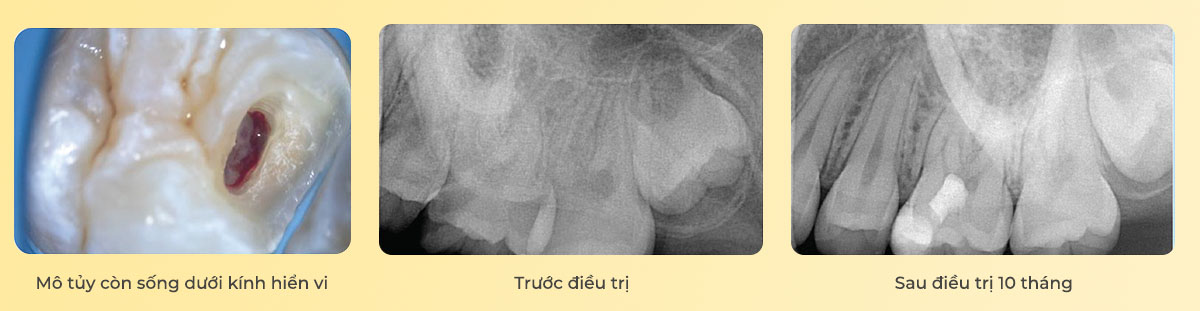

Module 1 cũng giới thiệu chi tiết điều trị bảo tồn tủy (Vital Pulp Therapy – VPT), từ chỉ định, kỹ thuật che tủy, lấy tuỷ buồng đến chiến lược phục hồi thân răng trước và sau điều trị nhằm đảm bảo tiên lượng lâu dài. Kết thúc module, học viên có sẽ tư duy chẩn đoán hợp lý, làm chủ kỹ thuật cô lập với đê cao su, lựa chọn và thực hiện VPT như một phần không thể tách rời của nội nha bảo tồn hiện đại.